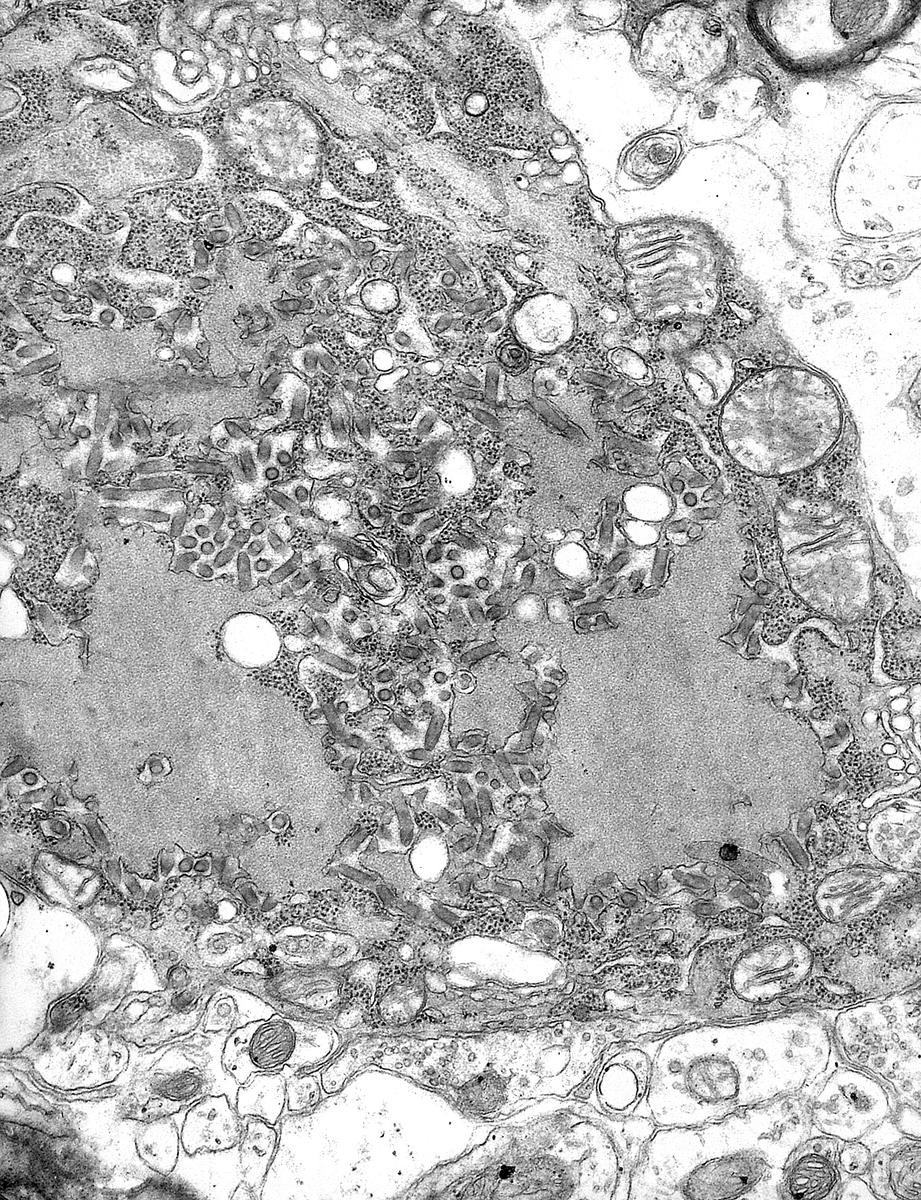

Вирус бешенства — нейротропный вирус (способный поражать нервные клетки) из семейства рабдовирусов. Имеет цилиндрическую форму и внешне больше напоминает бактерию, но нет — это вирус.

Вирус заражает нейроны и уже по ним добирается до гиппокампа, в цитоплазме клеток которого возникают новообразования — тельца Бабеша — Негри. Помимо гиппокампа, вирус проникает в слюнные железы, где начинает размножаться. Именно через слюну и передаётся данный вирус.

Жизненный цикл вируса начинается со связывания гликопротеина G с н-холинорецепторами, NCAM1 и др. Гликопротеин активирует рецептор-опосредованный эндоцитоз (захват клеткой внешнего вещества), вирус попадает в клеточные везикулы (специальные органеллы, с помощью которых происходит захват и попадание вещества из внешней среды в клетку). Путём конформационного превращения (изменения формы молекул) и снижения pH (кислотности) среды вирус сливается с оболочкой мембраны и попадает внутрь клетки. Капсид разрушается, РНК высвобождается и с помощью L- и P-белков происходит её репликация с образованием мРНК, которая попадает в рибосомы и начинает синтез вирусных белков. Остальные матричные РНК потом опять подвергаются репликации с образованием снова антисмысловой (-) РНК (которую и использует вирус). M-белок обеспечивает сборку всех этих частиц в вирион. Самым последним к вириону присоединяется новый гликопротеин G, так как начале он попадает на внешнюю сторону клетки, а оставшийся M-белок всё ещё внутри. Гликопротеин вновь делает всё тоже самое, только уже наоборот, обеспечивая вирусу возможность попасть сначала в везикулы, а потом уже, соединившись с вирионом, покинуть клетку и отправится к соседней клетке, чтобы повторить весь вышеописанный процесс.